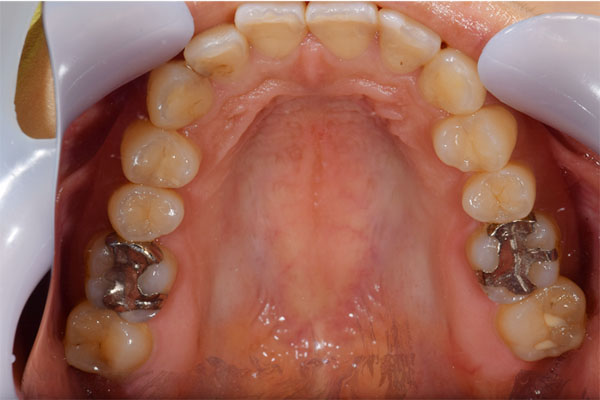

| 主訴 | 虫歯がたくさんあり、銀歯に穴が空いているのが気になる |

【担当医師所見】

左下奥歯は親知らずが原因でクラウン(かぶせ物)の下まで虫歯になっています。 またその手前の歯は根中央部に大きな透過像(黒い像)が見られます。クラウン除去後、マイクロスコープ下で確認したところ中央部は亀裂が入り保存不可能な状態になっており抜歯となりました。

また反対側の奥歯も古くなっており、将来性を考えセラミックへ変更しています。